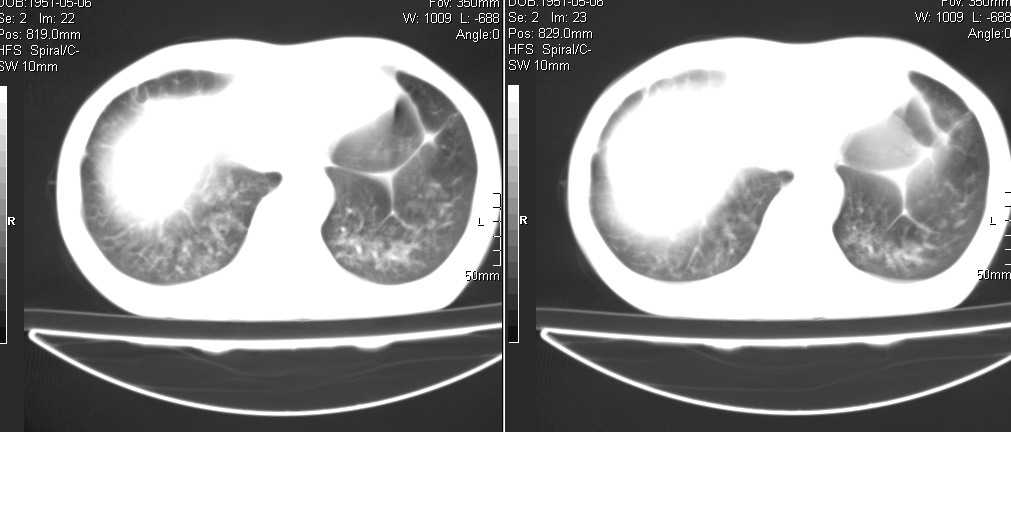

以下是引用光线在2008-5-6 18:36:00的发言:[br]双肺结核(左上肺空洞形成)、间质性改变合并感染,右肺大泡;右侧胸膜增厚。

以下是引用zsl6918在2008-5-7 1:54:00的发言:[br]首先肺泡蛋白质沉着症,其次考虑机遇性感染。